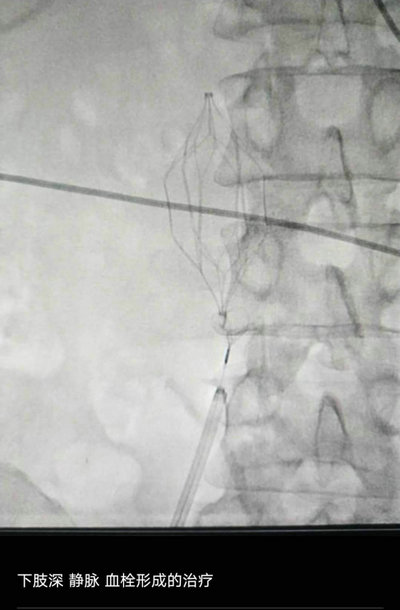

近日,我院介入科成功为骨外科二病区一名因右股骨上段骨折,左侧股浅静脉级胫后静脉有血栓形成的患者及时实施下腔静脉滤器置入术,有效地阻止了深静脉血栓脱落和在溶栓过程中血栓脱落引起的致命性肺动脉栓塞,为日后骨科医生给患者做骨折手术时保驾护航。下腔静脉滤器置入术的成功开展,标志着我院下肢深静脉血栓患者不用长途跋涉转诊,就能在我院进行治疗。

患者张某某,男,41岁,因车祸导致双下肢疼痛畸形伴活动受限,入院后确诊为右股骨上段骨折,左侧股浅静脉级胫后静脉有血栓形成(考虑不稳定血栓形成),在骨外科二病区李晓光主任、赵忠福副主任的指导下,邀请介入科马晓欧主任进行会诊,最终决定进行下腔静脉滤器置入手术。

4月8日下午13:30分,患者被送入介入治疗室,在做好相关术前准备后,介入科马晓欧主任及杜友利主治医师的配合下历时30分钟成功完成,将一把形似伞状的人工滤器经患者右侧股静脉穿刺迅速置入下腔静脉,“网”住了通往心血管和肺部的致命栓子。有了对付肺栓塞健康的“护身符”,术后患者无不适反应,顺利返回病房。(供稿:介入科 杜友利)

介入科主任马晓欧(右)、主治医师杜友利进行下腔静脉滤器置入术